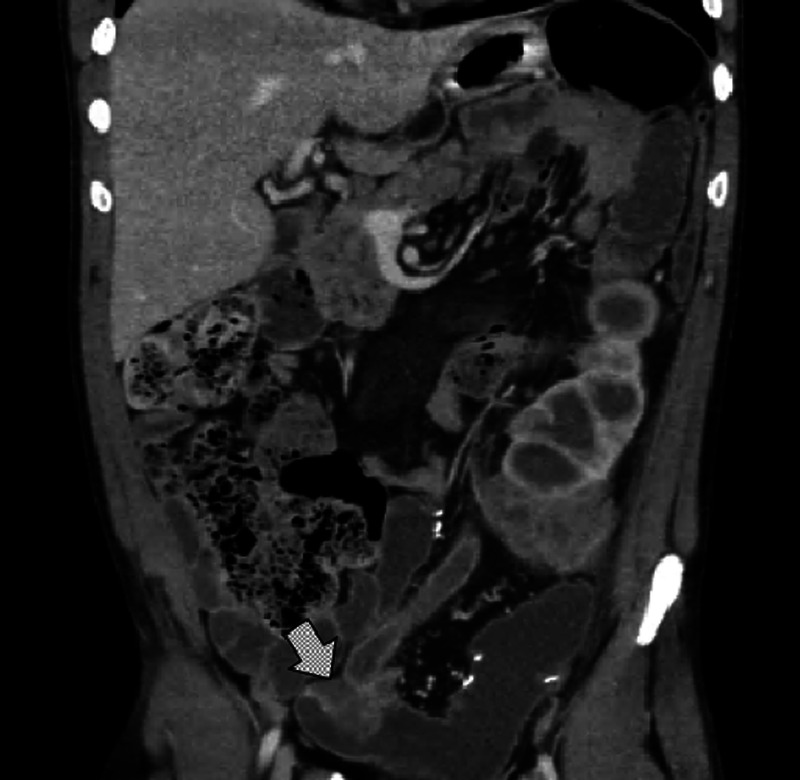

Ureterosigmoidostomy was commonly utilized as a procedure for continent urinary diversion. However, ureterosigmoidostomy is associated with complications such as infection, electrolyte disturbances, and neoplasia development. A 40-year-old Caucasian male presented with acute left flank pain. Past medical history was significant for bladder exstrophy for which ureterosigmoidostomy urinary diversion was performed during childhood. On physical exam, multiple circular erythematous patches were scattered across the forearms that had been presented for 2 years. Cross-sectional imaging demonnttated an ill-defined mass at the site of ureteral implantation with associated severe left hydroureteronephrosis. Endoscopy revealed a mass at the site of ureteral implantation and biopsy demonstrated invasive, poorly differentiated adenocarcinoma. The dermatosis was diagnosed as interstitial granulomatous dermatitis, a rare inflammatory skin condition associated with underlying autoimmune disease or malignancy. Patient elected operative management with left nephrectomy, sigmoidectomy, and ileal conduit diversion. Ihis case demonnttates a rare presentation of cutaneous paraneoplastic syndrome after development of colon cancer after ureterosigmoidostomy. Ureterooolonic urinary diversion has a demonnttaaie risk of neoplasia development at the anastomotic site, requiring routine endoscopic surveillance.